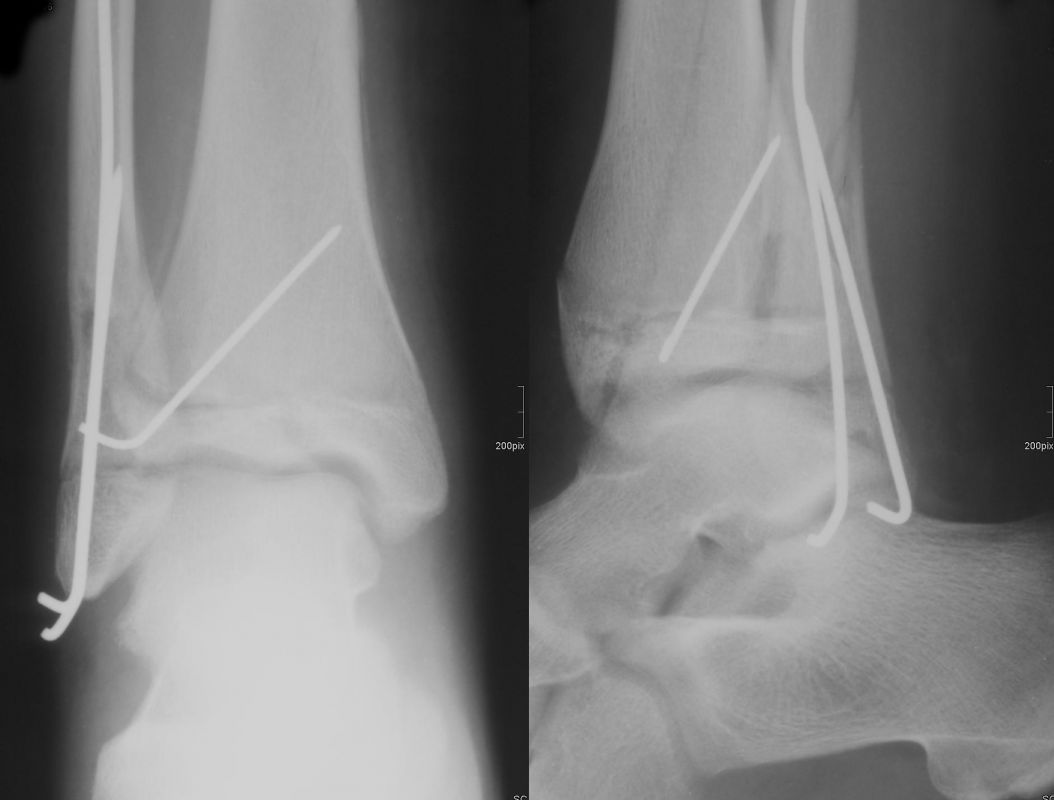

Findet sich eine Dislokation der Wachstumsfuge erfolgt nach Reposition eine K-Drahtspickung. Die postoperativ angelegte Gipsschale wird nach Abschwellung entfernt und ein Unterschenkelgips für 4 Wochen angelegt.

Nach Gipsabnahme können die Drähte entfernt und das Sprunggelenk zunehmend aufbelastet werden.

Sowohl nach konservativer als auch nach operativer Behandlung sind die Kinder 2-3 Wochen nach Gipsabnahme üblicherweise wieder gut mobil.